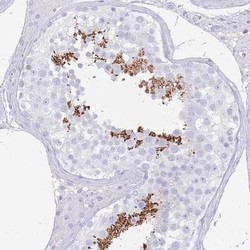

- Immunohistochemistry-Paraffin: C2orf57 Antibody [NBP2-14406] - Staining of human testis shows distinct positivity in a subset of cells in seminiferus ducts.